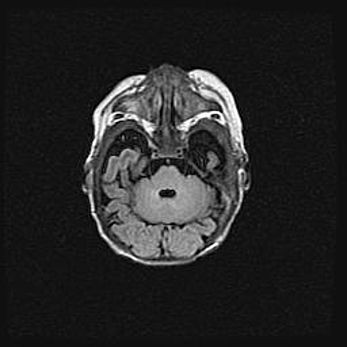

Открытая гидроцефалия.

Возраст: 6 месяцев 15 дней

Вес: 6200 г

Пол: женский

Окружность головы: 41 см

Срок гестации: 38 недель

Гидроцефалия головного мозга у новорожденных – это скопление избыточного количества цереброспинальной жидкости в головном мозге. Ее избыточное скопление в мозге приводит к патологическому расширению желудочков мозга (четырех полостей, расположенных в глубине белого вещества мозга, заполненных цереброспинальной жидкостью и связанных узкими проходами).

Открытый тип гидроцефалии (сообщающаяся) наблюдается тогда, когда нарушен механизм всасывания ликвора в системный кровоток. При этом типе причиной заболевания чаще всего является перенесенные ранее инфекции (например: менингит),  либо же наличие крови в субарахноидальном пространстве.